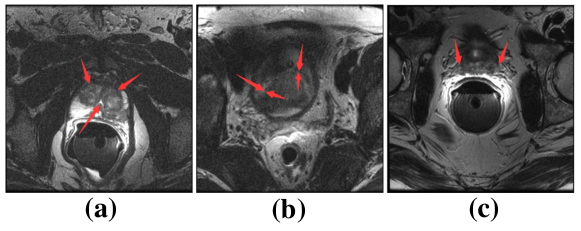

Medical image segmentation is an essential part of medical image analysis. Accurate segmentation of medical image provides very useful information for computer aided diagnosis and treatment of cancers as well as other diseaseszhu2019multi . For instance, segmentation of the liver and tumors plays an important role in hepatocellular carcinoma diagnosis heimann2009comparison . Accurate prostate segmentation is useful for treatment planning and therapeutic procedures for prostate cancerliao2013representation ; zhu2019boundary ; zhu2018exploiting . However, automated medical image segmentation is very challenging for several reasons. Taking prostate segmentation as an example: First, due to many slices only have small part of segmented tissues specifically at the apex and base, which always led to those slices lack of clear boundary and make the automated segmentation fail. Second, imaging artifacts always distribute in the whole image randomly, which negatively influence the process of segmentation. Third, tissues can have a wide variation in size and shape among different slices, which adds to the complexity of segmentation. Fourth, the complex background and fuzzy boundary also make the segmentation process challenging. Furthermore, different from natural images dataset, the size of available medical image dataset is limited. Fig.1 shows examples of prostate MR images. Fig.1(a) shows the phenomenon that imaging artifacts locate in prostate region. Fig.1(b) shows prostate region lacks clear boundary. Fig.1(c) shows the prostate and surrounding tissues have similar intensity distribution. All of above phenomena bring challenges for automated medical image segmentation.

Figure 1: Challenges in segmenting the prostate from MR images. (a) Noise inside prostate. (b) Weak boundary. (c) Surrounding tissues having similar intensity distribution with prostate.